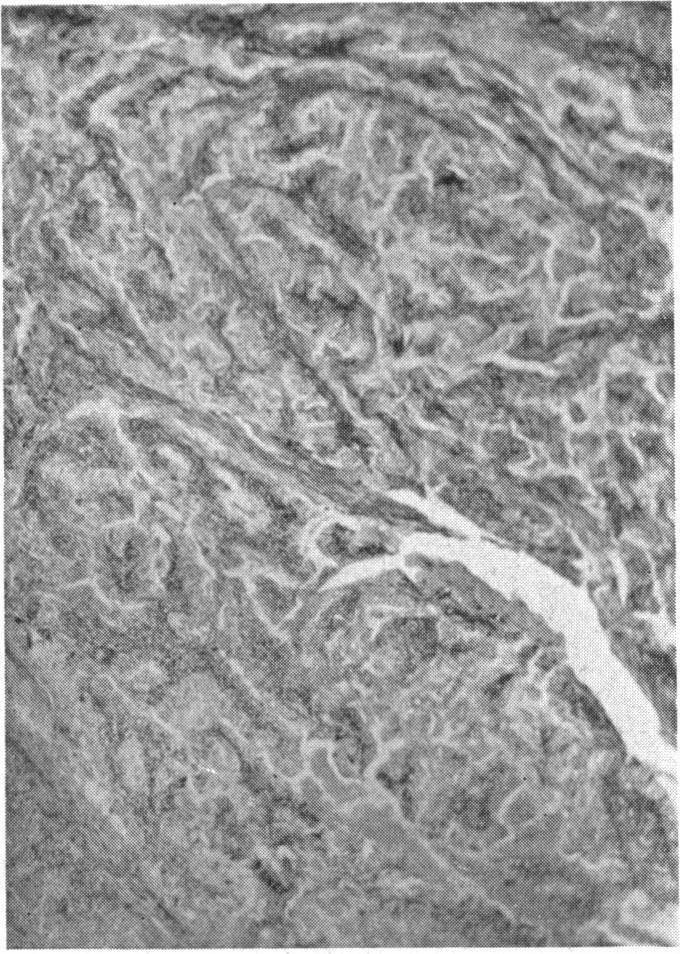

MALIGNANT TUMORS OF SYNOVIAL ORIGIN.

Ann Surg. 1942 Mar;115(3):413-26. doi: 10.1097/00000658-194203000-00009.